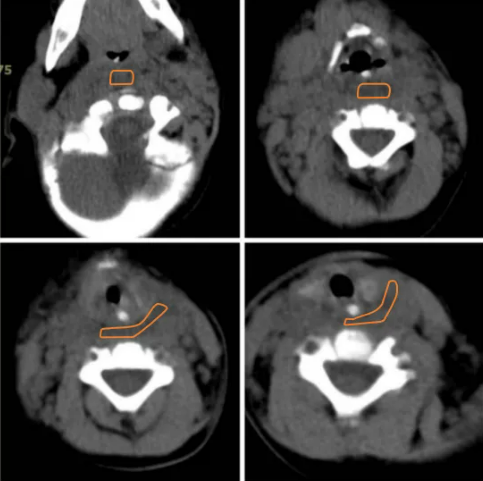

患儿抵达后,通过绿色通道,快速进入评估抢救流程。明确诊断:1.脓毒血症;2.咽后间隙脓肿;3咽旁间隙脓肿;4呼吸困难(2度)。遂快速送入手术室,通过经验丰富的麻醉医师充分评估,给予静脉麻醉、插管,保证患儿呼吸通道。耳鼻咽喉头颈外科经口腔检查,从咽后壁穿刺,抽出约20ml脓性分泌物,探查脓腔,引流出大量脓性分泌物,放置负压引流后转ICU,由儿科协助进行后续治疗,通过多学科通力合作,为重症婴儿恢复保驾护航,5天后,患者病情好转,转回当地医院。

2021.12.28当地医院影像

2021.12.30治疗后影像